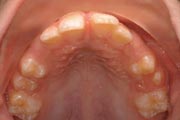

Crowding

Before